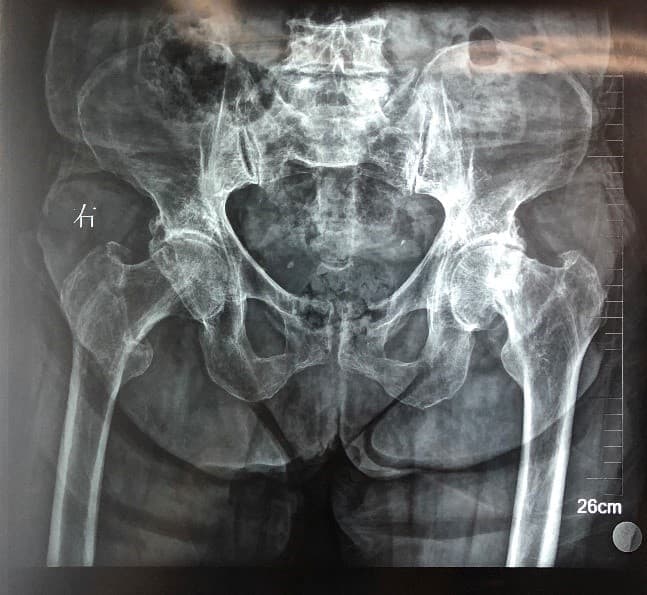

Мэс заслын өмнөх болон дараах зурагууд

Түнхний үе хагас солих мэс засал (Bipolar Hip QRL)image3Түнхний үе хагас солих мэс засал (Bipolar Hip QRL)image4